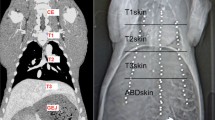

Three-dimensional modeling and point mapping

The segmented hepatic veins were converted to 3D polygonal models of the hepatic vein tree using the MITK software. Bifurcation points were used for point mapping, rather than center of vessel lumens because of the potential for achieving a greater consistency with the tools used. The first step was to determine the common bifurcation points within each pig separately, which adequately represented the central to peripheral range of the models. Points were mapped using the transverse, sagittal, and coronal views and were confirmed on the 3D models (Fig. 1). The amount of bifurcation points varied between pigs (7–16 points). Rare trifurcations were treated as bifurcations between the two largest of the three branches. The consistency of the points was then re-examined by an experienced radiologist. The use of branching points allowed reliable measurement of liver motion in different locations [42] (Fig. 2).